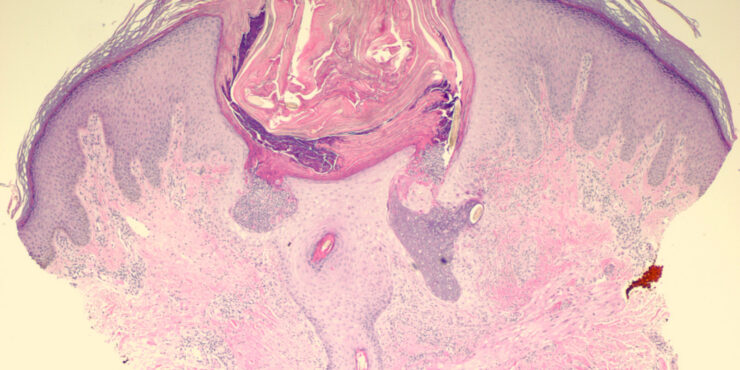

Parapsoriasis Large-plaque = نظير الصدف كبير اللويحات Parapsoriasis There are three entities described as parapsoriasis: small-plaque parapsoriasis, large-plaque parapsoriasis, and parapsoriasis variegata. Large-plaque parapsoriasis and parapsoriasis variegata are best considered as early stages of cutaneous T-cell lymphoma/mycosis fungoides. The small-plaque parapsoriasis is also known as xanthoerythrodermia perstans of Crocker and as digitate dermatosis . Pink-to-yellow, slightly scaly, oval or elongated, […]